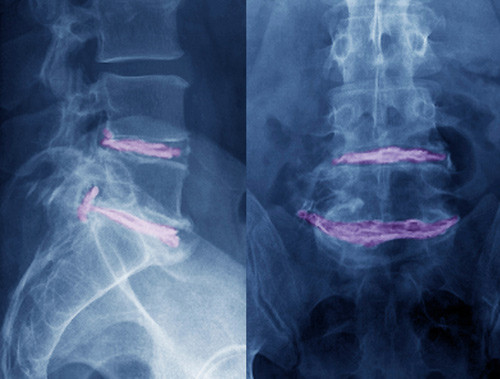

Pasienter med vedvarende eller residiverende isjias blir gjerne henvist til gjentatte MR-undersøkelser av ryggen. En nederlandsk forskergruppe har undersøkt sammenhengen mellom funn ved MR-undersøkelse og isjiasplager hos 267 pasienter ett år etter at de fikk isjias med MR-påvist skiveprolaps. 224 pasienter (84 %) var da helt eller nesten helt kvitt sine plager. Skiveprolaps og nerverotaffeksjon ble påvist på MR like hyppig hos pasientene som var blitt friske (henholdsvis 35 % og 24 %) som hos dem som hadde restplager eller nye isjiasplager (henholdsvis 33 % og 26 %). Prolapsens størrelse og type (skivebukning eller ekstrudert prolaps) var heller ikke assosiert med pasientens plager.

– Denne studien viser bildediagnostikkens begrensninger for å forklare hvorfor pasienter får ryggsmerter, sier Kjell Arne Kvistad, seksjonsoverlege ved Klinikk for bildediagnostikk, St. Olavs hospital. – I flere studier er det dokumentert at degenerative forandringer påvist på MR, inkludert skiveprolaps i lumbalryggen, har liten eller ingen korrelasjon til forekomst av ryggsmerter. Denne studien understreker at når pasienter med residiv av isjiassmerter etter prolapskirurgi skal vurderes for reoperasjon, er det sykehistorien og de kliniske funnene som er viktigst, ikke funn ved bildeundersøkelser, sier Kvistad.